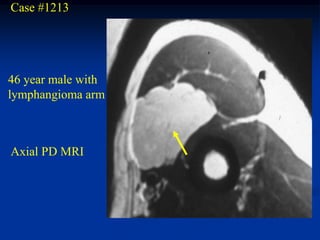

Case #1213

46 year male with

lymphangioma arm

Axial PD MRI

Case #1213 46 yearmale with lymphangioma arm Axial PD MRI

Coronal T-2 MRI vein showing lymphangioma next to cephalic vein

Sagittal T-2 MRI vessels showing hygroma next to brachial vessels